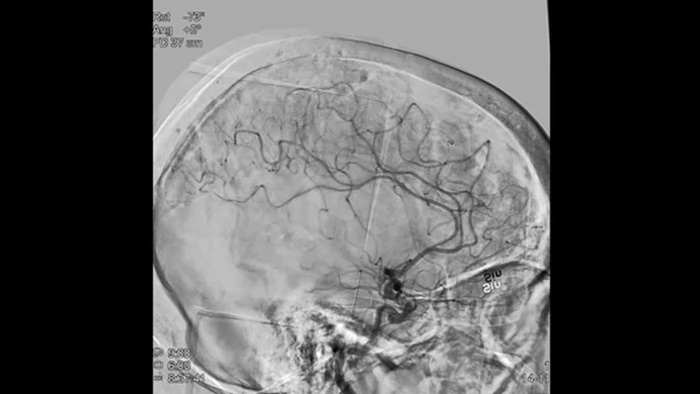

Imagens nítidas com DSA 2D com tecnologia ClarityIQ

DSA 2D com tecnologia ClarityIQ

O ClarityIQ aplica a compensação automática de movimento durante o DSA em tempo real para manter as imagens dos vasos nítidas. Isto suporta a tomada de decisões confiante ao longo dos procedimentos de acidentes vasculares cerebrais.

Visualização de DSA

As visualizações de DSA de alta qualidade permitem avaliar se a recuperação completa do coágulo foi alcançada e se partes de coágulo foram dispersas distalmente no cérebro. Pode verificar a restauração do fluxo sanguíneo para a penumbra e verificar se existe hemorragia peri-procedimento.